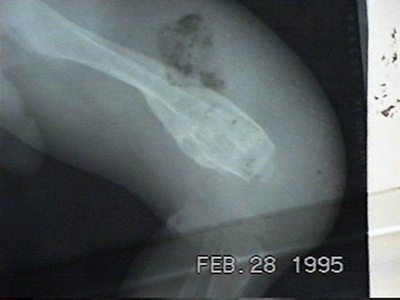

Osteomyelitis

Bone inflammation due to infection, often bacterial, causing deep pain, fever, and potential bone destruction. Requires prolonged antibiotics and sometimes surgery; early diagnosis prevents chronic disease.